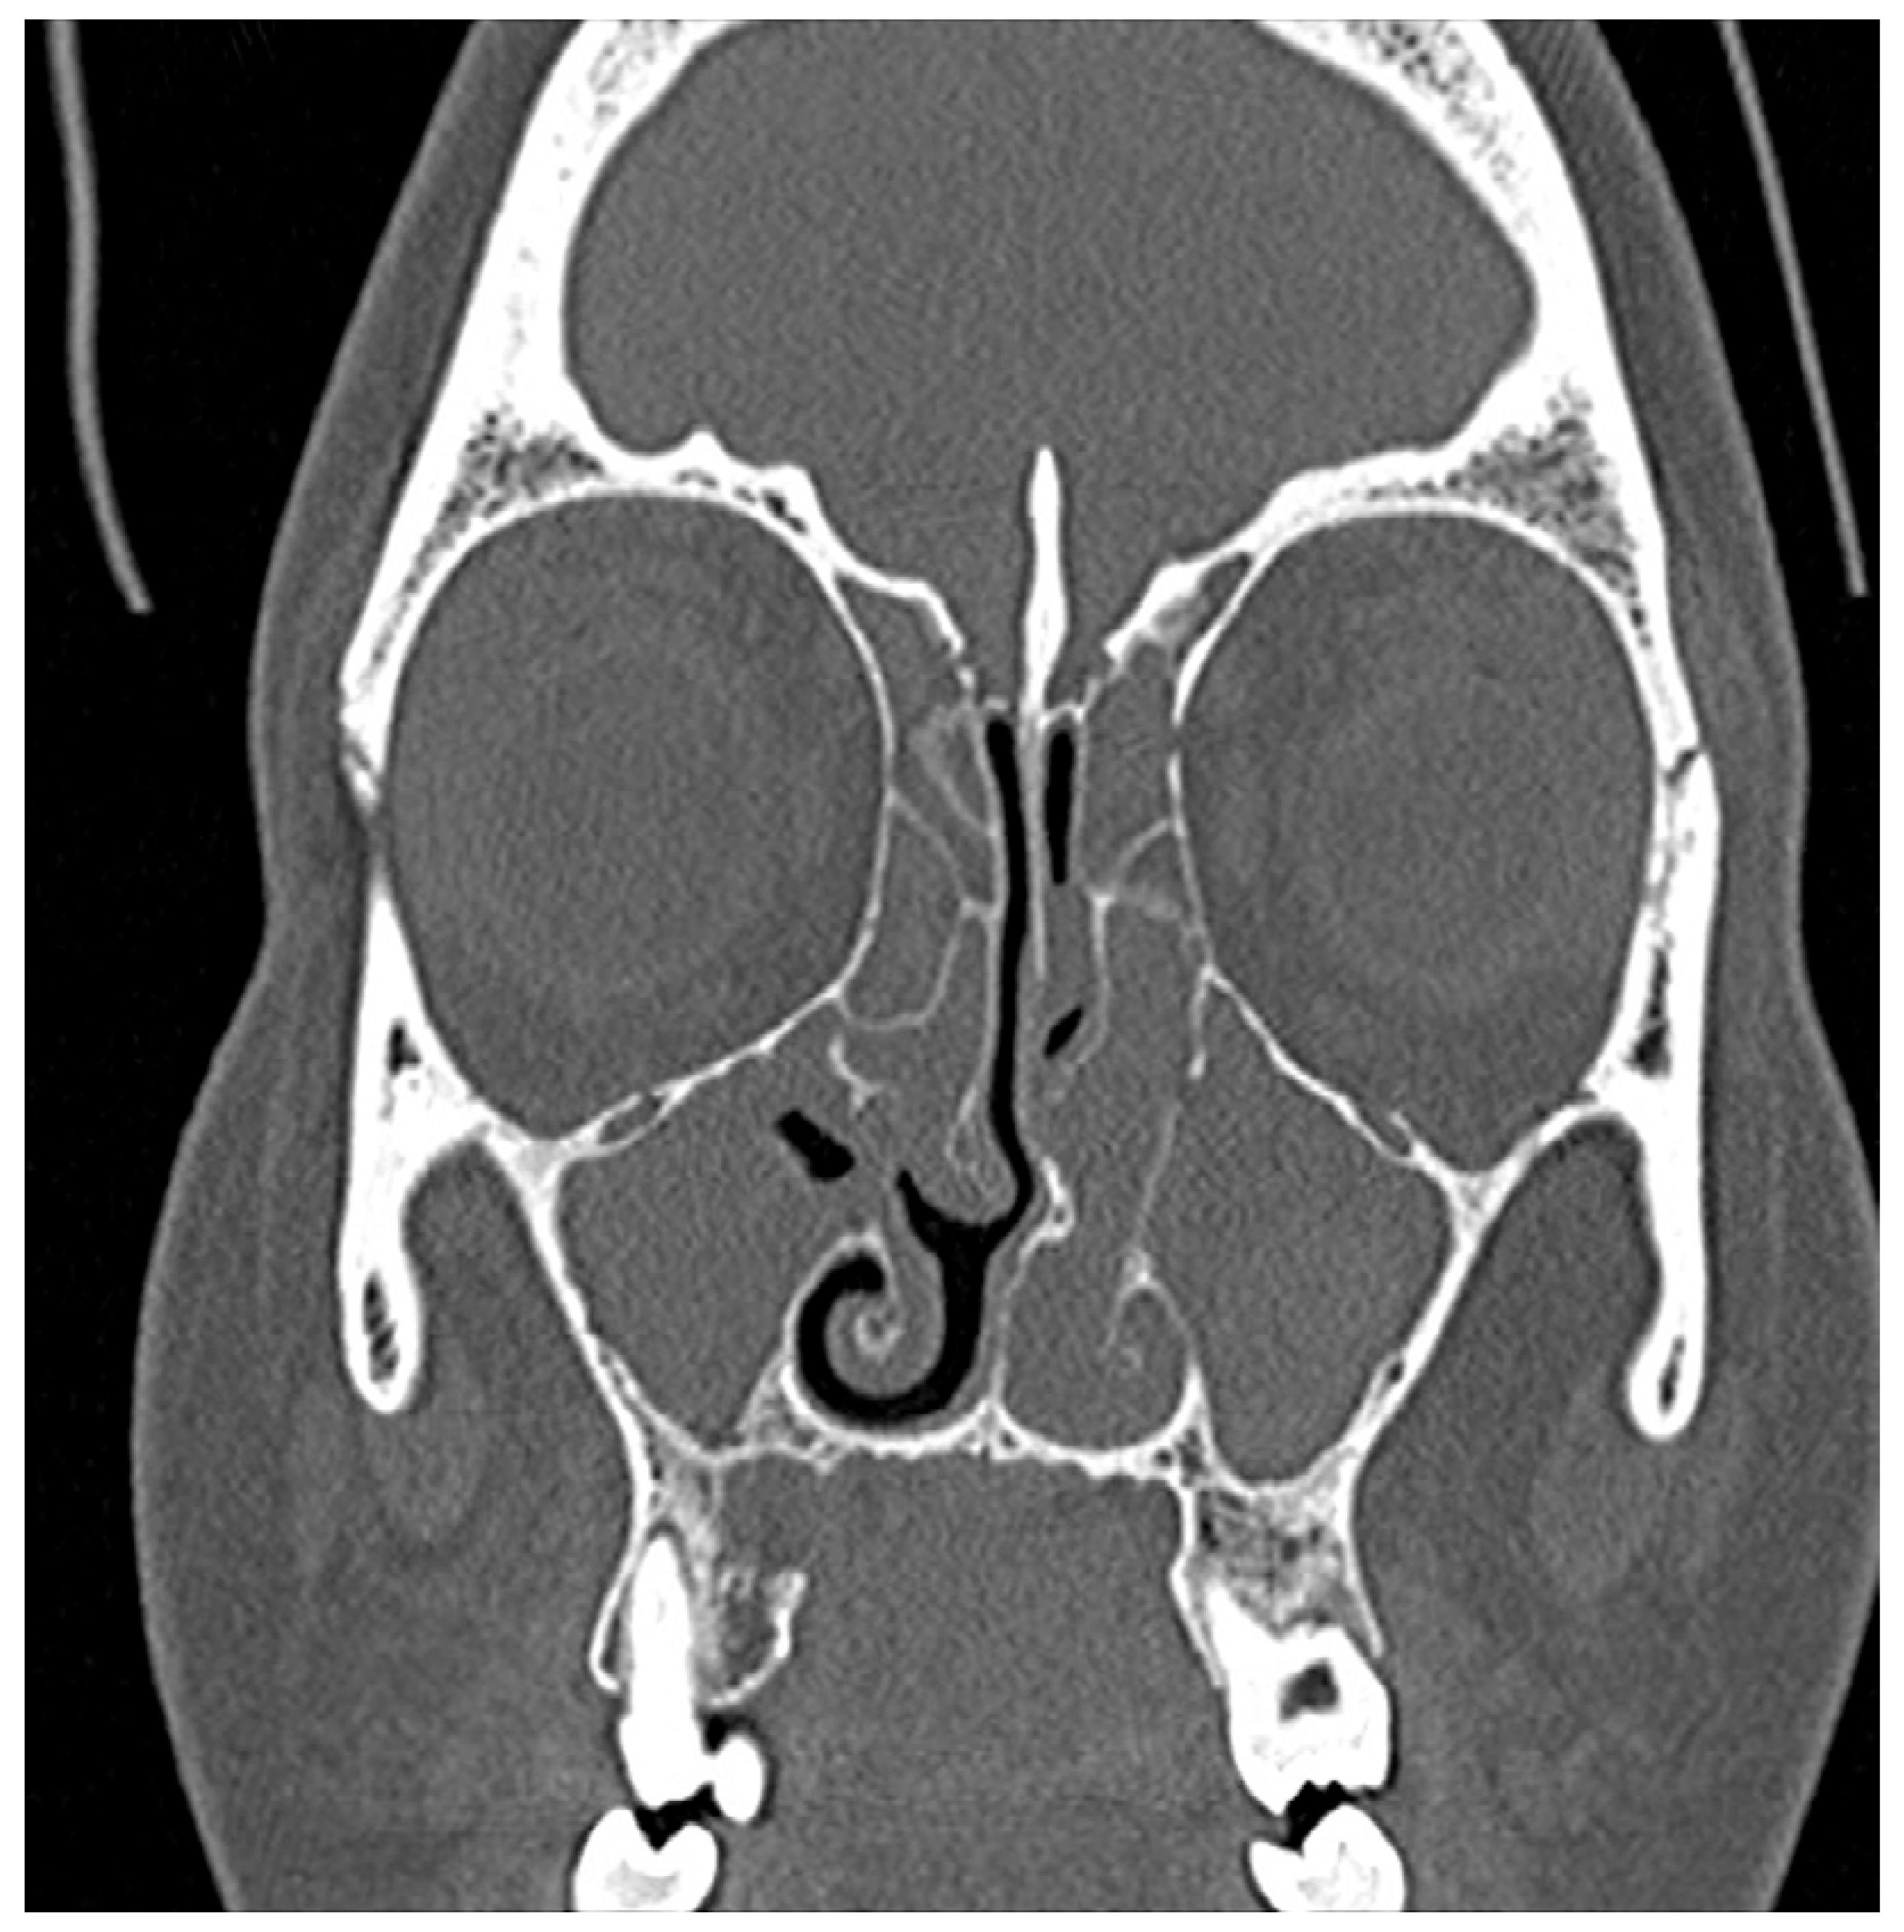

L’imagerie

Les images obtenues avec un scanner peuvent aider votre médecin à déterminer la taille et l’emplacement des polypes dans les zones plus profondes de vos sinus et d’évaluer l’étendue de l’inflammation. Ces images peuvent également aider votre médecin à exclure la présence d’autres obstructions possibles dans votre cavité nasale, telles que des anomalies structurales ou un autre type de lésions cancéreuses ou non cancéreuses.